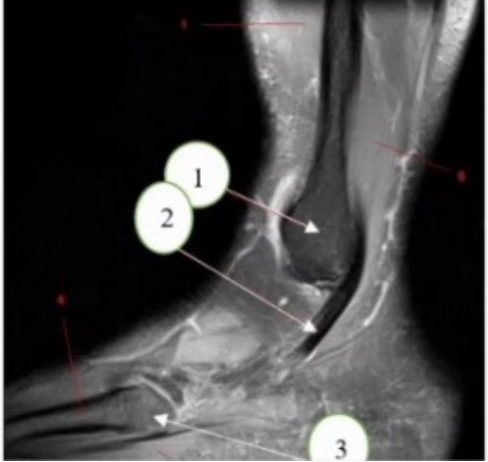

What kind of exam is this?

a. Wrist

b. Ankle

C. foot

What is the anatomical plain for the image above?

a. Axial

b. Sagittal

c. coronal

What anatomy is arrow 1 is pointing at?

a. Tibia

b. Fibula

c. Talus

What anatomy is arrow 2 is pointing at?

a. Pealajurti tendon

b. Peroneal tendon

c achillies tendon

d. Tibialis tendon

What anatomy is arrow 3 is pointing at?

a. 15 metacarpal tuberosity

b. 5 metatarsal tuberosity

C 15 melatarsal tuberosity